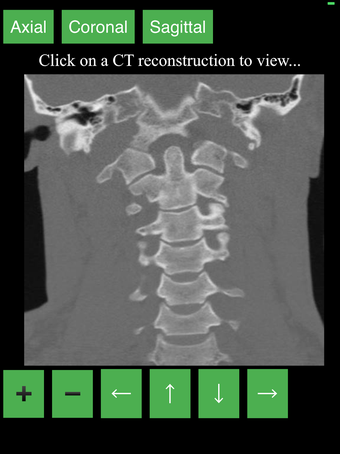

Перекрестные разрезы данных КТ предоставляют динамический и интерактивный метод просмотра поперечной анатомии человека. Вы можете вращать, увеличивать и перемещать изображение, чтобы изучать любую часть тела в деталях.

Перекрестные разрезы создаются с помощью комбинации математических алгоритмов для интерпретации данных из серии сканирований. Результирующие изображения затем преобразуются в серию 2D поперечных срезов и отображаются в специальном приложении для просмотра.